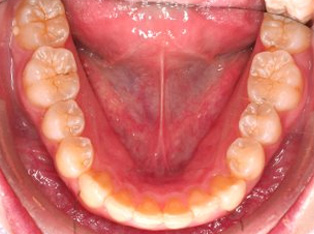

でこぼこがある状態になります。乱ぐい歯とも言われます。見た目がよくない審美障害が主な問題点ですが、その他にもでこぼこが多いことで、歯ブラシによる清掃性が悪くなり、結果、虫歯や歯周病のリスクも上がってしまいます。治療期間が短く済むことも多い為、気になった段階で早期に相談された方が良いと思います。